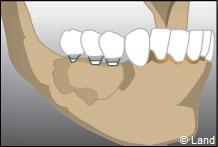

LES GREFFES D’APPOSITION

Elles sont indiquées dans les insuffisances d’épaisseur.

Les différentes étapes :

Prélèvement du greffon au niveau du site donneur

Apposition et stabilisation du greffon.

Recouvrement du greffon avec de l’os synthétique et une membrane

Après 6 mois de cicatrisation, il est possible de poser les implants qui recevront dans un deuxième temps les couronnes.